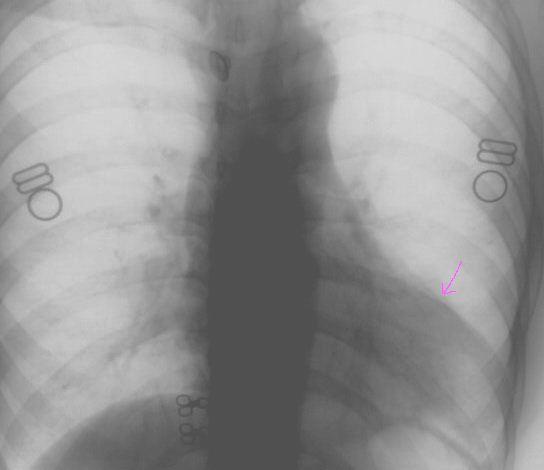

标题: X5295:大家看看,是肺上病变还是心脏上的。

女,23岁,体检。

室壁瘤?肺部占位?肺疝?建议侧位片或ct检查。

哪里?是心尖部吗?应该是心脏与肋骨、乳房的重叠形成的构成影。心右缘肺野密度增高,考虑肺心动脉,不除外肺部病变,建议侧位或ct

考虑左下肺病变;建议行ct扫描检查。

透视下,病灶随心脏搏动,外缘不光整。